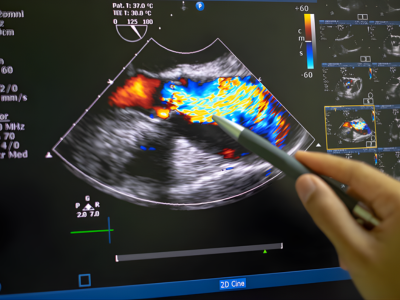

State-of-the-Art Cardiac Imaging & Diagnostics at Echelon Hospital

Early and precise diagnosis is the foundation of effective cardiology treatment in Navi Mumbai. Echelon Hospital is equipped with advanced diagnostic tools that help detect heart conditions at an early stage.

These technologies enable cardiologists to evaluate heart function, identify blockages, and assess overall cardiovascular health with accuracy.